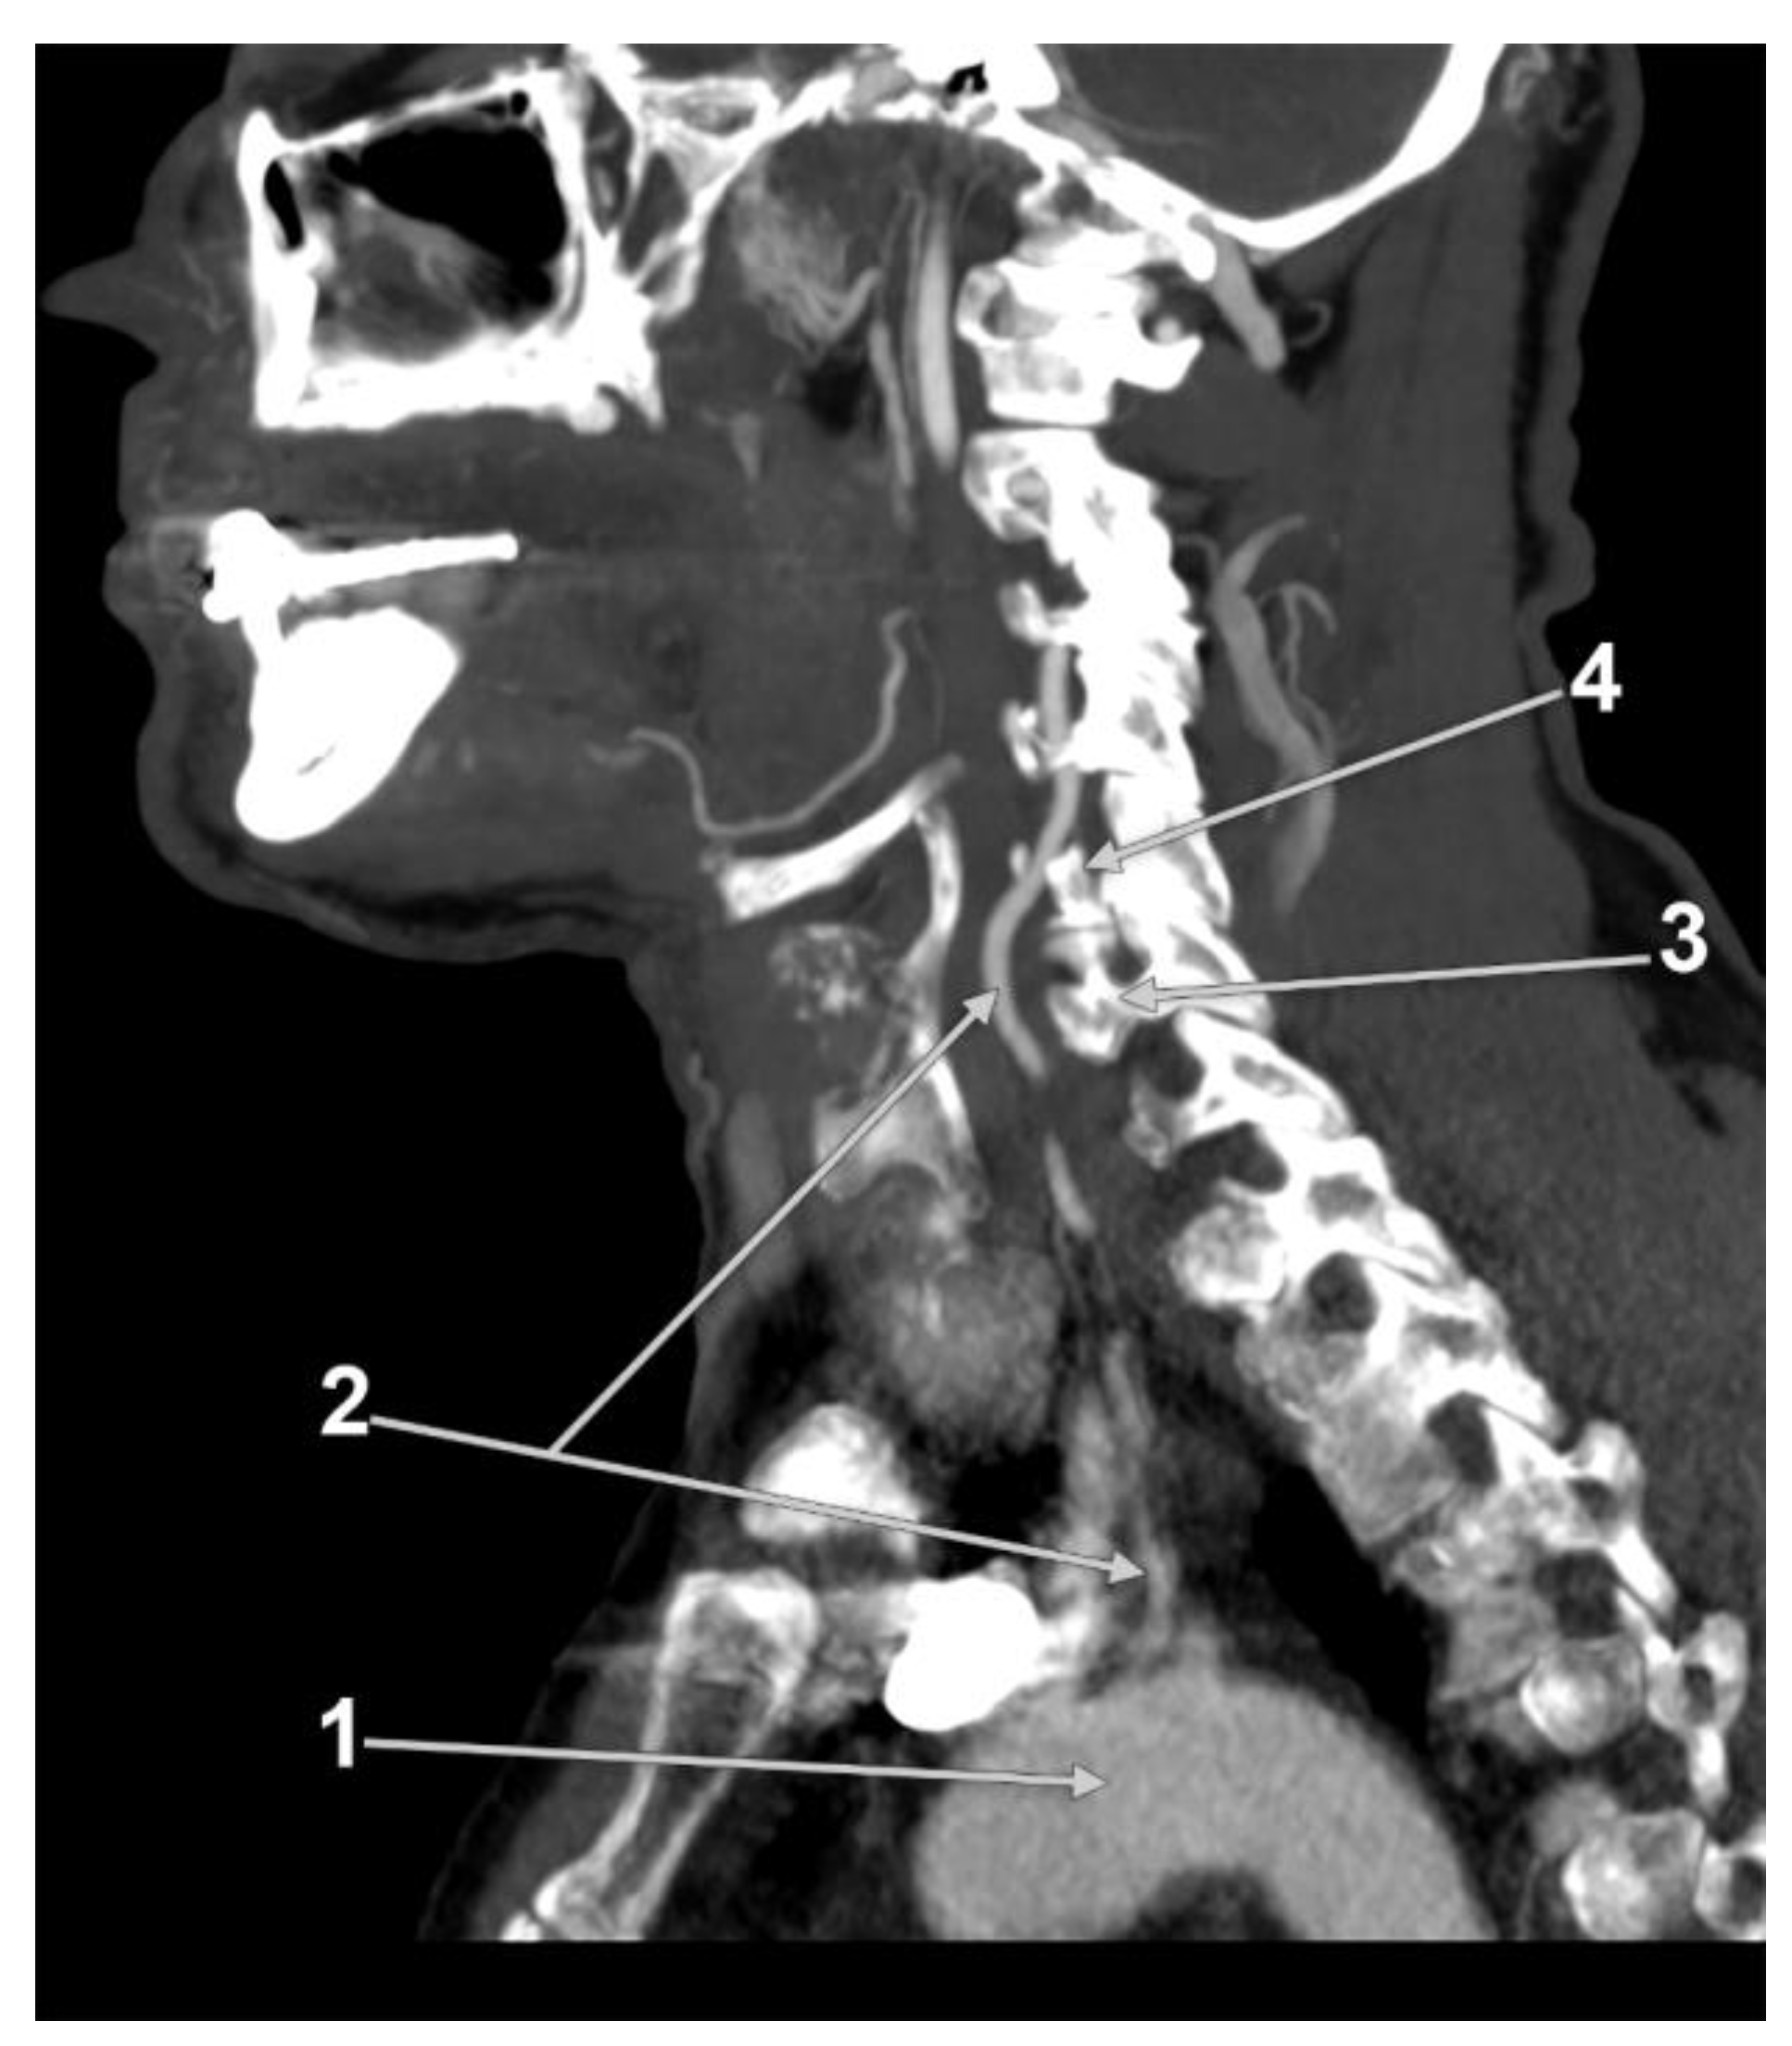

3.5. Prevalence of the VA Course

3.5.1. Tortuosity

3.5.2. Straight V1 Segment Prevalence